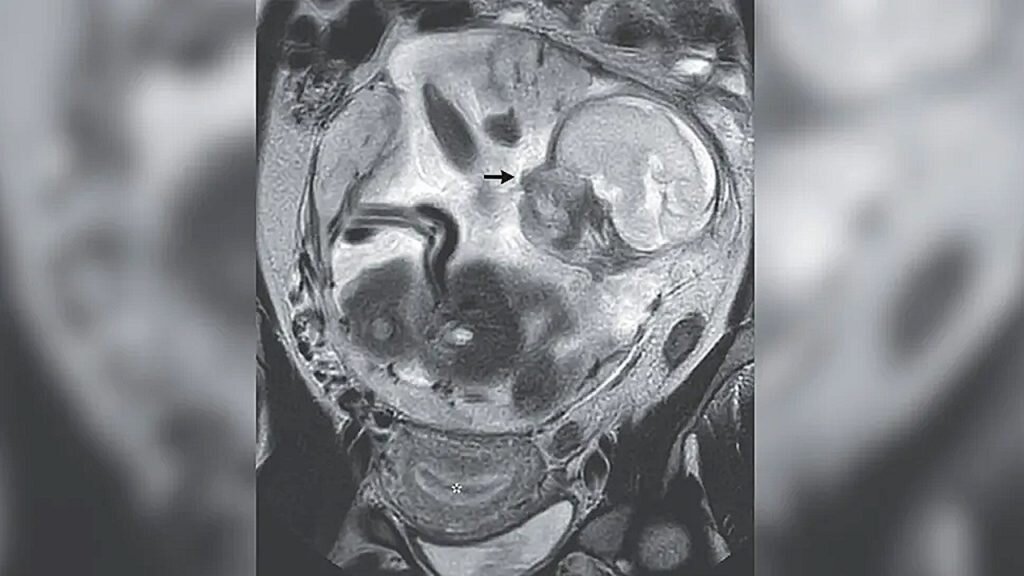

Магнитно-резонансная томография (МРТ) показала, что ребенок был «нормально сформирован» и прикреплен к плаценте. Она была прикреплена к слизистой оболочке живота у основания позвоночника женщины.

Обложка: МРТ показало, что ребенок женщины рос в животе (черная стрелка), а не в матке (отмечено звездочкой). Изображение предоставлено: The New England Journal of Medicine ©2023